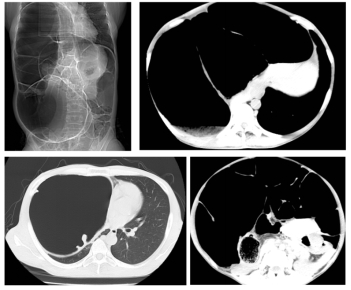

家住佳木斯40岁的陈女士,被便秘困扰20余年,长期遭受便秘的折磨,近年间症状持续加重,排便周期长达7日并伴随剧烈腹胀。陈女士在哈尔滨医科大学附属第一医院群力院区行CT检查,腹腔内盲肠、升结肠、横结肠、降结肠及部分乙状结肠严重扩张积气,移行段位于乙状结肠,以造成右侧膈肌上移压迫右肺。群力院区普外科一病房(结直肠外科)朱跃坤教授诊断为特发性巨结肠。